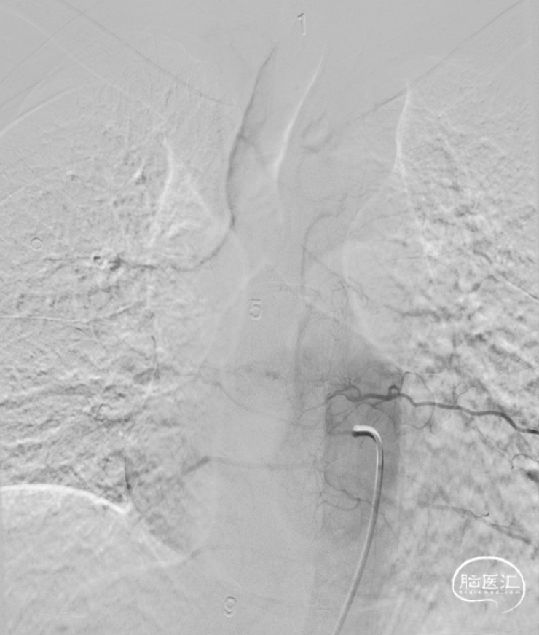

术前影像(2024-02-20, 脊髓血管造影)

image.png

· 通过胸腰椎MRI检查大多可见到血管流空影,进一步脊髓血管造影可以明确诊断。